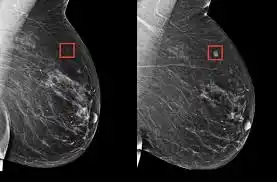

IA puede identificar mujeres con RIESGO ELEVADO DE CÁNCER DE MAMA varios años antes del diagnóstico

IA revoluciona la detección del cáncer de mama: examinan mamografías con precisión

Cáncer de mamas puede ser detectado gracias a la Inteligencia Artificial